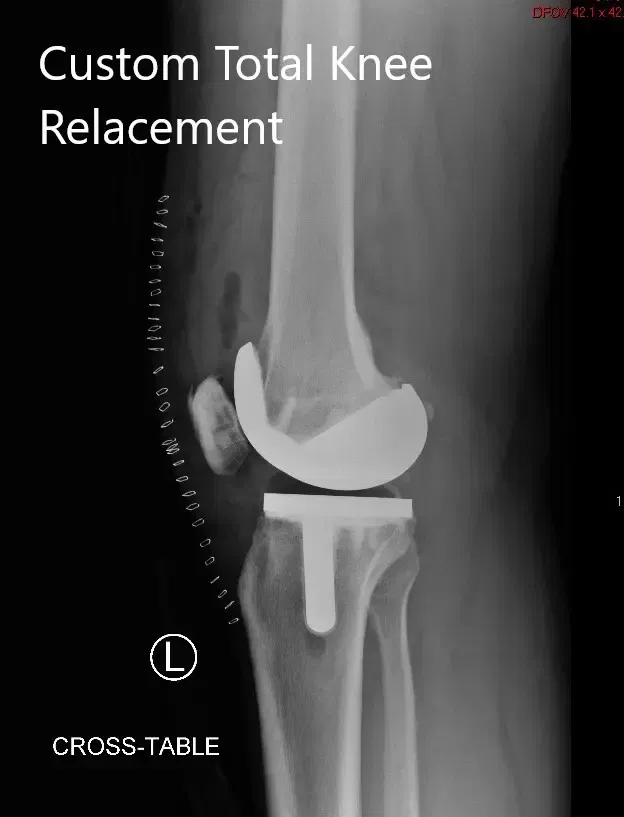

OPERACIÓN: Artroplastia total de rodilla izquierda usando implantes de rodilla personalizados. Los implantes utilizados fueron implantes femorales con una bandeja tibial personalizada con inserto de polietileno de 16 mm con

Implante rotuliano de 29 mm x 6 mm.

Radiografía postoperatoria de la rodilla izquierda que muestra vistas laterales y AP